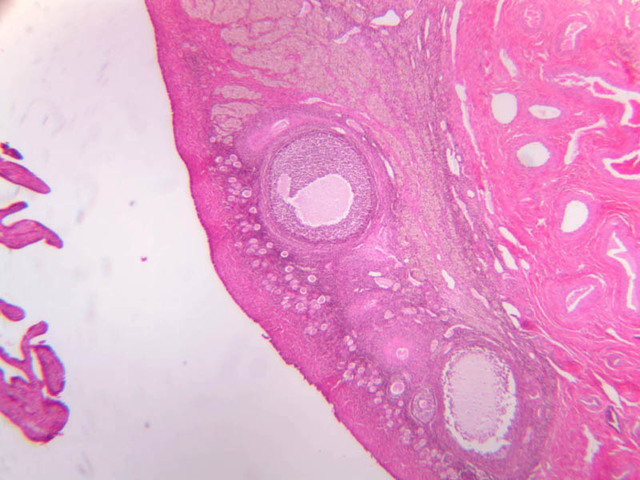

The ovary is a somewhat oval and slightly flattened organ situated near the fimbriated end of the uterine tube (B-94, monkey ovary, H&E [1x, 1x]; B-95, monkey ovary, H&E [1x-labeled, 1x]; B-96, monkey ovary and tube, H&E [1x]; B-54, H&E [1x, 1x]). Its exposed surface is covered by a mesothelial sheet of squamous or cuboidal epithelium. Just deep to this is an ill defined area of dense fibrous connective tissue referred to as the tunica albuginea (B-96 [2.5x-labeled, 10x-labeled, 20x, 40x]).

The ovary has two major regions – the cortex and the medulla. The cortex is the broad peripheral area containing follicles in various stages of development, whereas the medulla is the more central area displaying profiles of large blood vessels. These blood vessels gain entrance via the mesovarium. The division between the cortex and medulla is indistinct. In the cortex, stromal cells occupy the areas between the follicles. These cells are closely packed, fusiform (spindle shaped), and have the potential to differentiate into a specialized component of the maturing follicle (theca folliculi).

Primordial follicles are located in periphery of cortex. They contain a large round oocyte surrounded by a single layer of flattened follicular cells. The follicles occupying this category are inactive. They are the population from which follicular growth begins. Primordial Follicles [Inactive] (slide B-94 [2.5x, 10x, 20x, 40x] [10x, 20x, 40x-labeled] [10x, 20x, 40x]; B-96 [2.5x, 10x, 20x, 40x, 40x, 40x, 40x]).

Secondary Follicle

• Early (vesicular stage)

• With continued granulosa cell proliferation, spaces filled with fluid (liquor folliculi) appear within this layer.

• Later (antral stage)

• Continued follicular enlargement occurs and the irregular spaces within the granulosa layer merge to form a single crescentric cavity, the antrum.

• Those granulosa cells immediately surrounding the zona pellucida become columnar and are referred to as the corona radiata.

• The theca folliculi begins to segregate itself into two distinct layers.